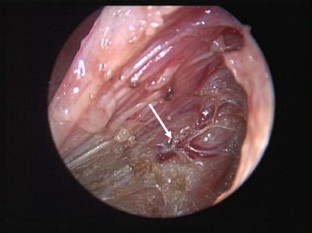

Fig. 1

Fig. 2